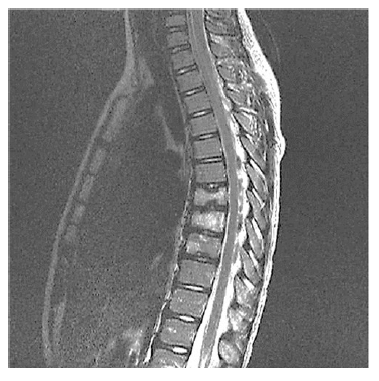

Um paciente de 15 anos de idade com queixas crônicas de dorsalgia (mais de um ano), leva à consulta ressonância magnética de coluna total apresentada. Não há outras queixas.

Acerca desse caso clínico e dos conhecimentos médicos correlatos, julgue os itens a seguir.